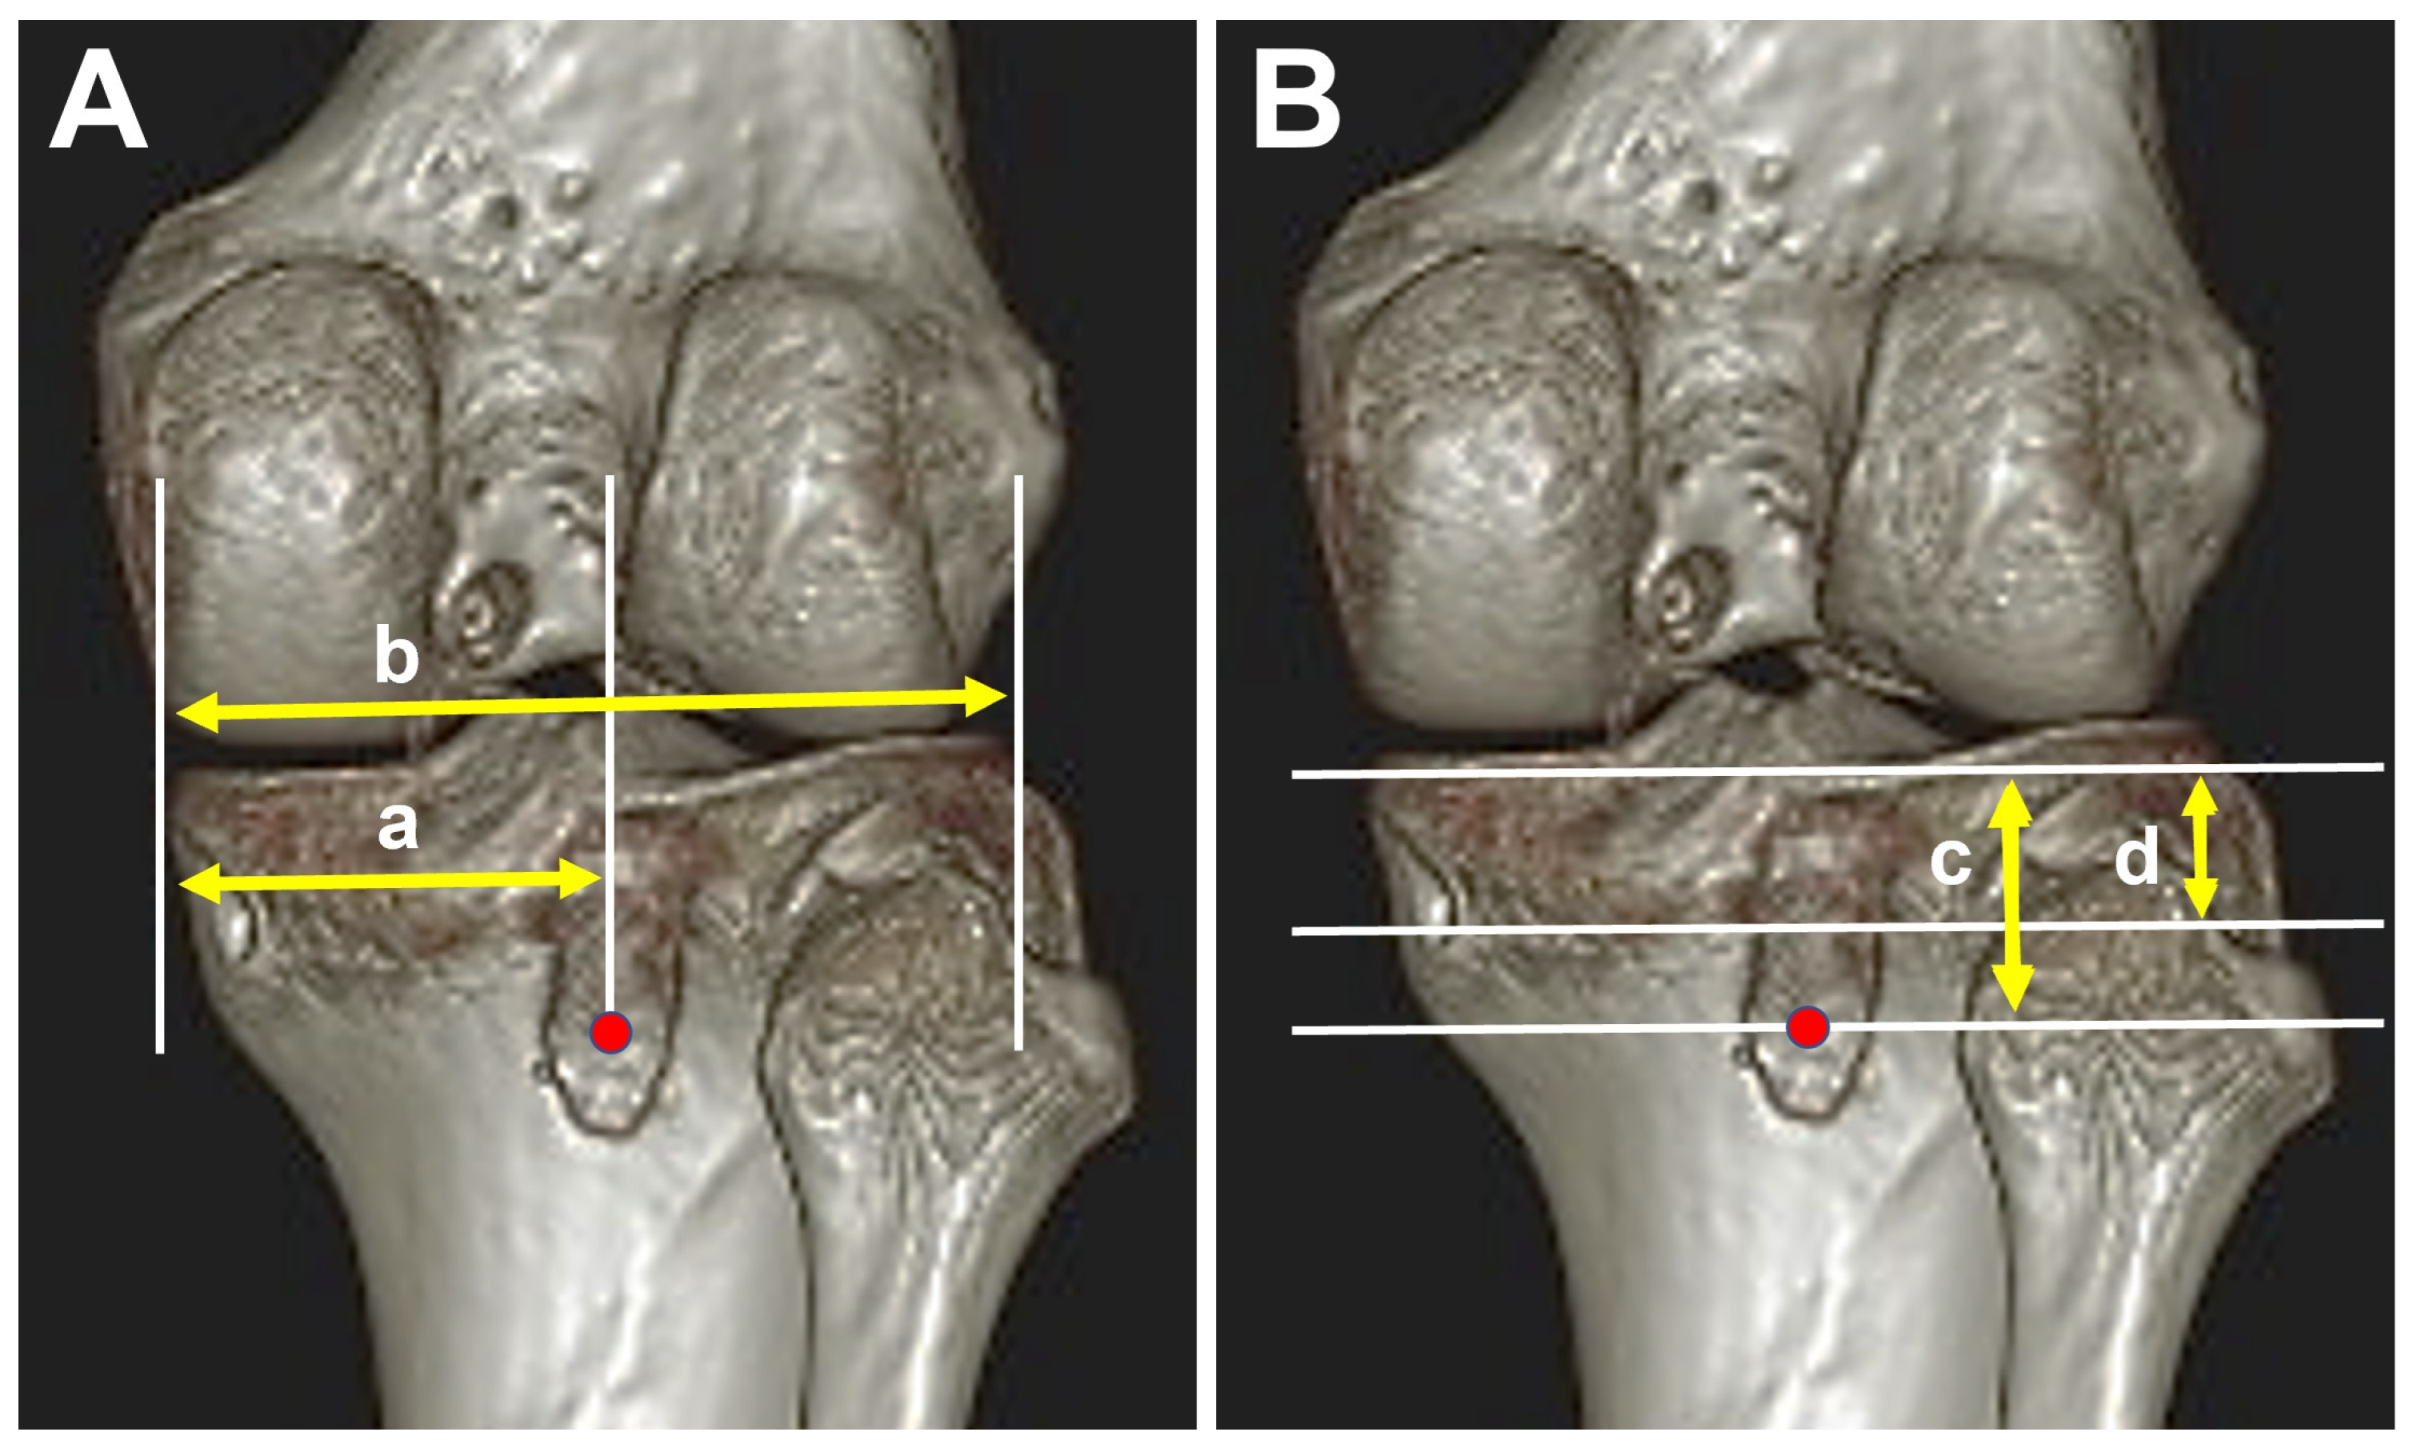

2.4. Evaluation of Tibial Tunnel Position on 3-Dimensional Computed Tomography (3D-CT)

3.2. Tibial Tunnel Position on 3D-CT Scan